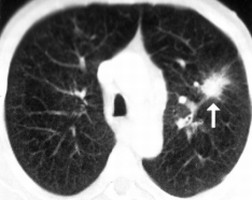

A CT (komputertomográfia) a hagyományos röntgen vizsgálat továbbfejlesztett változata, amely kitűnő térbeli és kontrasztfelbontású képet ad a test anatómiai viszonyairól. Az eljárás során harántmetszeti (keresztmetszeti) felvételeket készítenek a test vizsgálandó részéről, melyeket egy számítógép összegez, és az orvos számára értékelhető képet alkot.

Az adott terület röntgensugár elnyelőképességének vizsgálatából, illetve annak változásából az esetleges kóros folyamatok (daganatok, sérülések, vérzések) meglétére, és azok pontos helyére lehet következtetni.

Az összes testtáj (koponya, gerinc, mellkas, has, végtagok) és valamennyi szervrendszer (idegrendszer, tüdő, hasi szervek, váz- és izomrendszer) keresztmetszeti vizsgálatára alkalmas. Kimutathatók vele a daganatok, gyulladások, sérülések, vérzések. A CT-angiográfia pedig az erek rendellenességeinek - értágulat, trombózis - kitűnő ábrázolását teszi lehetővé.